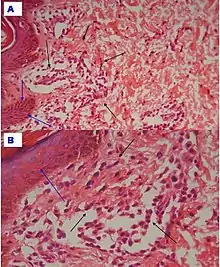

| Urticaria, lymphocyte predominant | Perivascular location. Mast cells are relatively sparse, potentially demonstrated with special stains, preferably tryptase stain. Extravasated erythrocytes are present in about 50% of the cases. No vasculitis.[14] |  Dermal edema [solid arrows in (A,B)] and a sparse superficial predominantly perivascular and interstitial infiltrate of lymphocytes and eosinophils without signs of vasculitis (dashed arrow).[15] Dermal edema [solid arrows in (A,B)] and a sparse superficial predominantly perivascular and interstitial infiltrate of lymphocytes and eosinophils without signs of vasculitis (dashed arrow).[15] |

| Urticaria, lymphocyte predominant | Perivascular location. Mast cells are relatively sparse, potentially demonstrated with special stains, preferably tryptase stain. Extravasated erythrocytes are present in about 50% of the cases. No vasculitis.[14] |  Dermal edema (solid arrows) and a sparse superficial predominantly perivascular and interstitial infiltrate of lymphocytes and eosinophils (dashed arrow) Dermal edema (solid arrows) and a sparse superficial predominantly perivascular and interstitial infiltrate of lymphocytes and eosinophils (dashed arrow) |